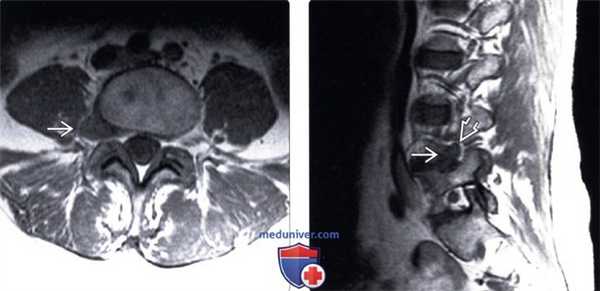

(Слева) Т2-ВИ, сагиттальный срез: языкообразная протрузия диска L4-L5. Наибольший краниокаудальный размер протрузии равен размеру ее основания, поэтому термин «протрузия» здесь следует считать наиболее подходящим.

(Справа) Т2-ВИ, аксиальная проекция: небольшая фокальная протрузия межпозвонкового диска L4-L5 справа, распространяющаяся в области выхода корешка L5. (Слева) Т1-ВИ, сагиттальный срез: крупная грыжа диска L3-L4, фрагмент которой мигрировал вниз до уровня 14 позвонка, что соответствует секвестрации диска (свободному фрагменту).

(Справа) Т2-ВИ, сагиттальная проекция: крупная экструзия диска, характеризующаяся относительно низкой интенсивностью сигнала и мигрировавшая кау-дально. Видны признаки значительного оттеснения грыжей вентрального листка дурального мешка. (Слева) Т2-ВИ, сагиттальный срез: массивная грыжа диска L4-L5, полностью сдавливающая дуральный мешок и вызывающая тяжелую компрессию корешков конского хвоста. Грыжи меньшего размера также присутствуют на уровнях L3-L4 и L5-S1.

(Справа) Т1-ВИ, сагиттальный срез: фораминальная экструзия диска L4-L5, перекрывающая собой периневральную клетчатку. Имеет место импинджмент выходящего корешка L4.